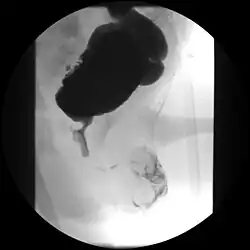

Subvesicale Obstruktion bei Urethralklappe

Unauffällige Urethra, aber beidseitiger Reflux

Die Diagnose wird aufgrund der charakteristischen Wandverdickung mit Unregelmäßigkeiten im Ultraschall gestellt und mittels Miktionszystourethrogramm bestätigt.